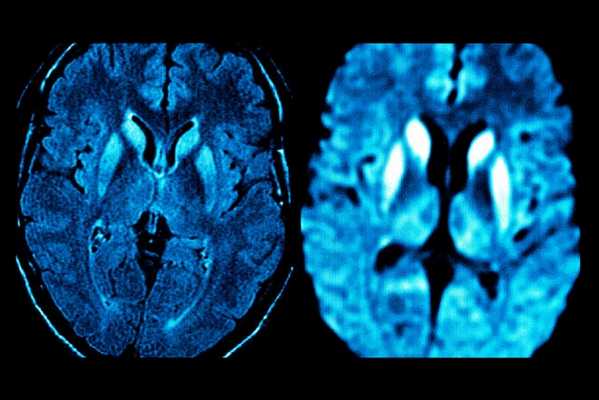

Одним из наиболее информативных среди современных методов нейровизуализации является метод МРТ диагностики.

Только благодаря современным программам, используемым в МРТ диагностике, стало возможным распознавание признаков нарушения мозгового кровообращения уже в первые 24 часа.

Первые часы ОНМК. Изменения в области правого островка демонстрирует только программа DW insult.